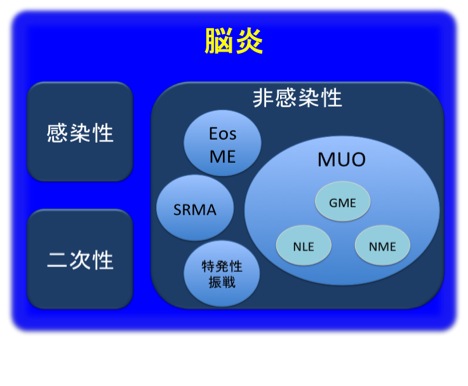

原因による脳炎の分類

脳炎は、その原因によって感染性、非感染性(特発性、免疫介在性とよばれることもあります)、二次性(他の脳疾患に続発して起こるもの)の3つに分類されます。犬の場合は感染性のものよりも非感染性の方の発生数が多く、猫ではその反対であるのが特徴です。

◯感染性脳炎の原因となる病原体には、種々の細菌、寄生虫(トキソプラズマなど)、真菌(クリプトコッカスなど)、ウイル ス(犬ジステンパーウイルス、猫免疫不全症ウイルス、猫伝染性腹膜炎ウイルスなど)などが存在します。

◯非感染性脳炎の大部分は、“起源不明の髄膜脳脊髄炎(MUO:meningoencephalomyelititis of unknown origin)”です。MUOには肉芽腫性髄膜脳脊髄炎(GME)、壊死性髄膜脳炎(NME)(以前はパグ脳炎とも言われていました)、壊死性白質脳炎(NLE)(チワワ脳炎と呼ばれることがあります)が含まれます。MUOの発生原因は未だ完全には解明されておりませんが、好発犬種が存在することと、多くの症例が免疫抑制治療によって改善を認めるという世界的な治療成績の集積から、遺伝性の自己免疫性疾患であることが強く示唆されております。その他の非感染性脳炎に、ステロイド反応性髄膜脳脊髄炎(SRMA)、好酸球性脳脊髄炎(EosME)、特発性振戦症候群があります。

◯ 二次性脳炎の原因としては、周囲(口腔、鼻腔、中/内耳)からの炎症・感染の波及、脳腫瘍、脳梗塞、頭部外傷などが挙げられます。